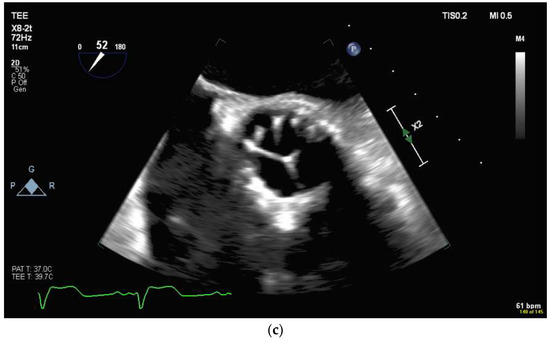

4.2.3. Mitral Valve Repair

4.2.4. Atrial Septal Defect Occlusion